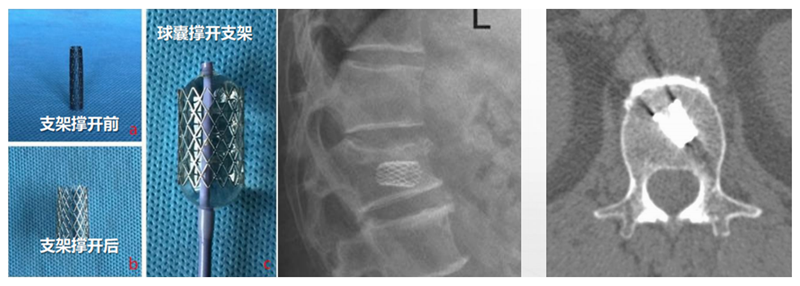

PCKP的优势在于术中操作安全、便捷、骨水泥弥散好,渗漏率低。术中穿刺过程中穿刺针以更小的穿刺角度进入椎体内,通过弯角骨钻开腔越过椎体中线,增加了穿刺安全区间,减少了术中医源性穿刺损伤的风险;同时通过弯角球囊的独特设计,可以在椎体中部造成弧形空腔,引导骨水泥在灌注过程中从穿刺对侧开始弥散,沿球囊撑开的弧形空腔充分灌注,达到单侧穿刺、双侧弥散的效果,有效降低了骨水泥渗漏风险。

(1)定位与穿刺:透视下确定伤椎椎弓根外缘上1/3 入路点及伤椎上终板或下终板方向并做好标记。由于穿刺容错率高,穿刺针(4. 2 mm)不用过度内倾,不必苛求针尖在椎体内侧壁、后壁位置,穿刺针从椎弓根外缘沿椎弓根方向缓慢穿刺入椎体即可,针尖务必穿刺入椎体后1/3。

(2)弯角导丝开腔:弯角骨钻开腔器械刺入椎体时,注意开腔工具手柄与伤椎终板平行,不要强行开腔,多透视侧位,否则弯导丝可能穿破终板,导致医源性骨水泥渗漏。C形臂X线机正位透视下,导丝到达椎体对侧椎弓根处即可。

(3)弯角骨钻扩张:C形臂X线机正位透视下,弯角骨钻开腔器械螺旋手柄顺时针扭转,让弯角骨钻沿导丝前进开路,将椎体内部钻出弧形通道。操作中注意骨钻沿导丝旋进旋出要完全,旋进不够,后期球囊无法到达对侧,旋出不完全,骨钻会卡在工作套筒上无法拔出。

(4)置入球囊:插入带导丝弯角球囊时注意透视球囊方向,反复调整务必与终板平行。如需要拔出球囊调整方向,务必先拔导丝再拔球囊,透视球囊标记点必须完全从工作套管内出来,否则易造成弯角球囊与工作套管边缘卡磨破裂。

(5)扩张球囊:注入造影剂扩张球囊过程中,注意观察术中正侧位透视图像,控制压力值,不必苛求球囊顶到上下终板,以免发生医源性终板破裂,造成椎间隙骨水泥渗漏可能。注意弯角球囊扩张完毕后拔除顺序:先拔导丝再拔球囊。

(6)注入骨水泥:应用骨水泥灌注管灌注骨水泥时,由聚醚醚酮树脂制成的灌注管在骨水泥灌注完成后要及时拔除,避免椎体内骨水泥硬化后无法拔出;椎体穿刺侧骨水泥灌注不满意,可拔除输送套管,直接连接穿刺套管,进行二次灌注。

术后行影像学检查,显示骨水泥弥散满意,达到了单侧穿刺,双侧弥散的效果,无渗漏